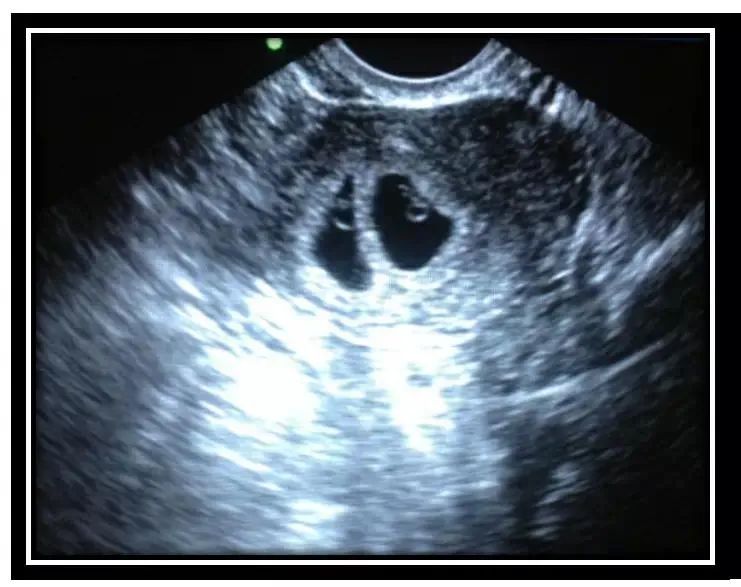

胎体未成形伤害小:怀孕35-55之间时,孕妇体内的孕囊大小刚刚合适,孕囊既可以B超下清晰体现,又还未形成完全的胎体,不需要扩宫就能轻松施术,对孕妇伤害小。